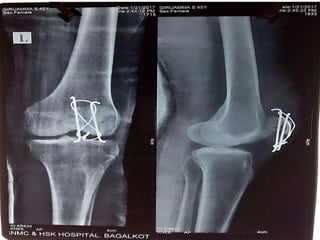

Investigations

X-RAY

X-RAY of left leg showing Fracture of patella